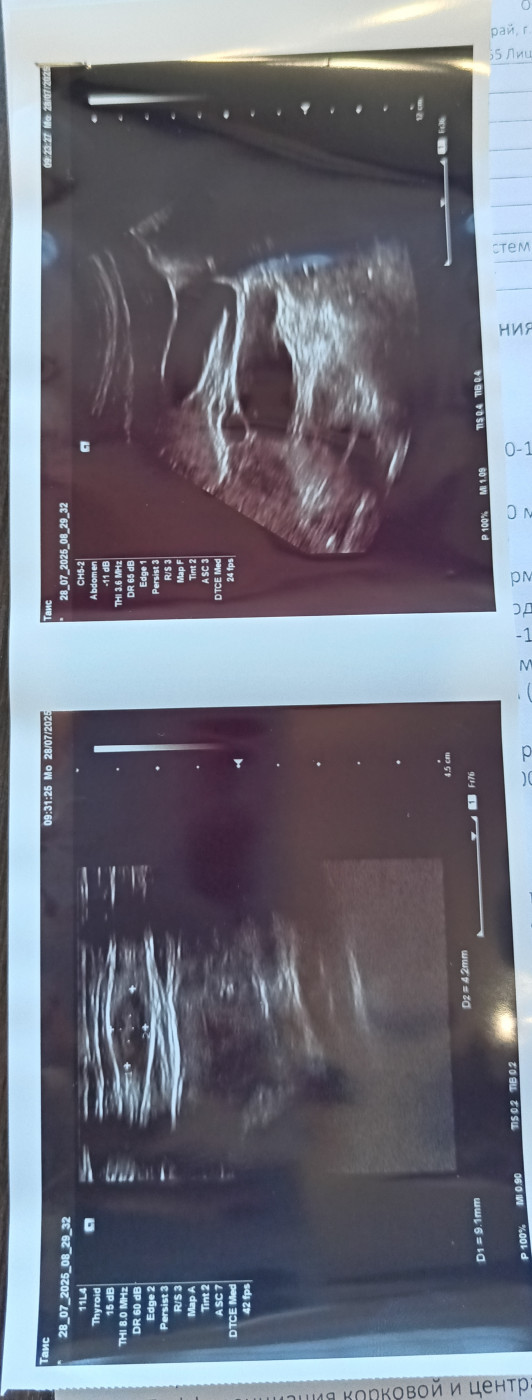

Лимфоузел или нет?Здравствуйте. Месяца 4 назад рядом со шрамом от аппендицита нащупала уплотнение. Стоя хорошо прощупывается,достаточно плотное маленькое, лежа трудно прощупать. Операция была 17 лет назад. Хирург сказал это липома, узи показало лимфоузел. После обследования прошло 2 месяца, уплотнение не прошло. Я читала, что в это области никак не нащупать лимфоузел. Нормально ли это? |

Здравствуйте. Для уточнения ситуации стоит выполнить УЗИ повторно (возможно, у другого специалиста), выполнить общий анализ крови. |